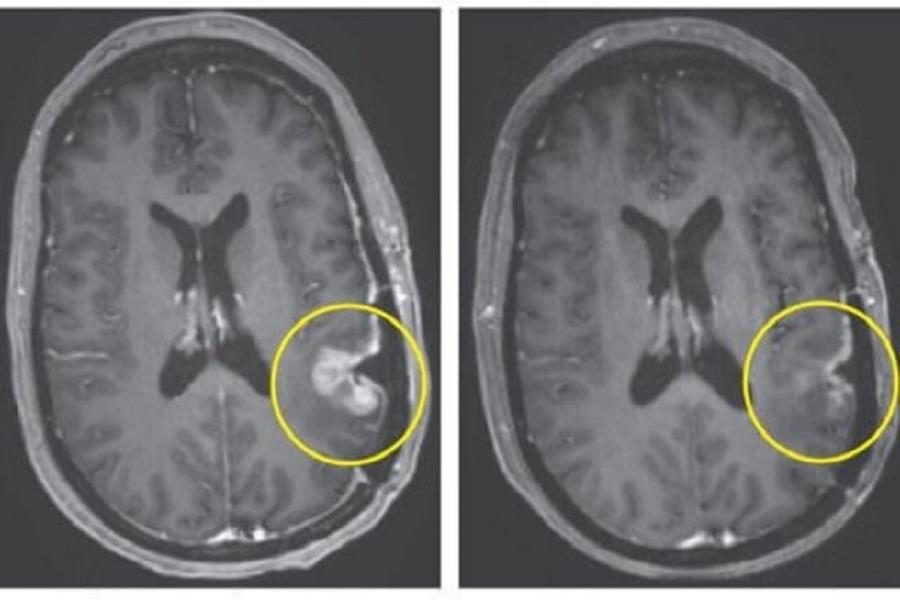

امیدهای تازه برای درمان سرطانهای مغزی

پژوهشگران با معرفی نسل جدیدی از نانوذرات هوشمند، افق تازهای را برای درمان بیماریهایی گشودهاند که تاکنون «درمانناپذیر» تلقی میشدند؛ فناوریای که میتواند پروتئینهای مخرب را در بدن شناسایی، هدفگیری و بهطور فعال نابود کند و امیدهای تازهای برای درمان سرطانهای مغزی، زوال عقل و بیماریهای خودایمنی به همراه داشته باشد.

مقالهای چشماندازمحور که بهتازگی در نشریه معتبر «نیچر نانوتکنولوژی» (Nature Nanotechnology) منتشر شده است، از معرفی یک فناوری نانوذرهای تحولآفرین خبر میدهد که توانایی حذف پروتئینهای بیماریزا از بدن انسان را دارد. این فناوری میتواند نقطه عطفی در دارودرمانی پروتئینهایی باشد که تاکنون «غیرقابلداروگیری» تلقی میشدند؛ پروتئینهایی که نقش محوری در بروز بیماریهایی همچون دمانس، سرطان مغز و اختلالات پیچیده ایمنی دارند.

با این حال، ابزارهای متداول این حوزه با چالشهایی جدی مواجهاند؛ از نفوذپذیری ضعیف در بافتها گرفته تا اثرات خارجازهدف و پیچیدگیهای سنتزی. این محدودیتها موجب شده است که کاربرد این روشها در بیماریهای مغزی و تومورهای جامد با موانع جدی روبهرو شود. به گفته پژوهشگران، راهبرد مبتنی بر نانوذرات معرفیشده در این مطالعه، بسیاری از این گلوگاهها را برطرف میکند.

از جمله مزیتهای کلیدی این فناوری میتوان به توانایی تخریب پروتئینهای داخلسلولی و خارجسلولی، هدفگیری اختصاصی بافت و بیماری حتی از میان سد خونیـمغزی، ساختار ماژولار «وصلوبازی» برای تطبیق سریع با اهداف پروتئینی متنوع، قابلیت تولید مقیاسپذیر و انطباق با الزامات بالینی با استفاده از مواد نانویی مورد تأیید سازمان غذا و داروی آمریکا، و امکان ادغام همزمان کارکردهای تشخیصی و درمانی اشاره کرد.

این فناوری که تحت پوشش چندین پتنت بینالمللی قرار دارد، در مطالعات پیشبالینی نتایج امیدوارکنندهای در برابر اهداف مهمی مانند EGFR، پروتئین محرک رشد تومور، و PD-L۱، عامل فرار سلولهای سرطانی از سیستم ایمنی، نشان داده است. پژوهشگران معتقدند این دستاورد مسیر را برای کاربردهای گسترده در انکولوژی، نورولوژی و ایمونولوژی هموار میکند و تعریف ما از نقش نانوذرات در پزشکی را دگرگون میسازد.